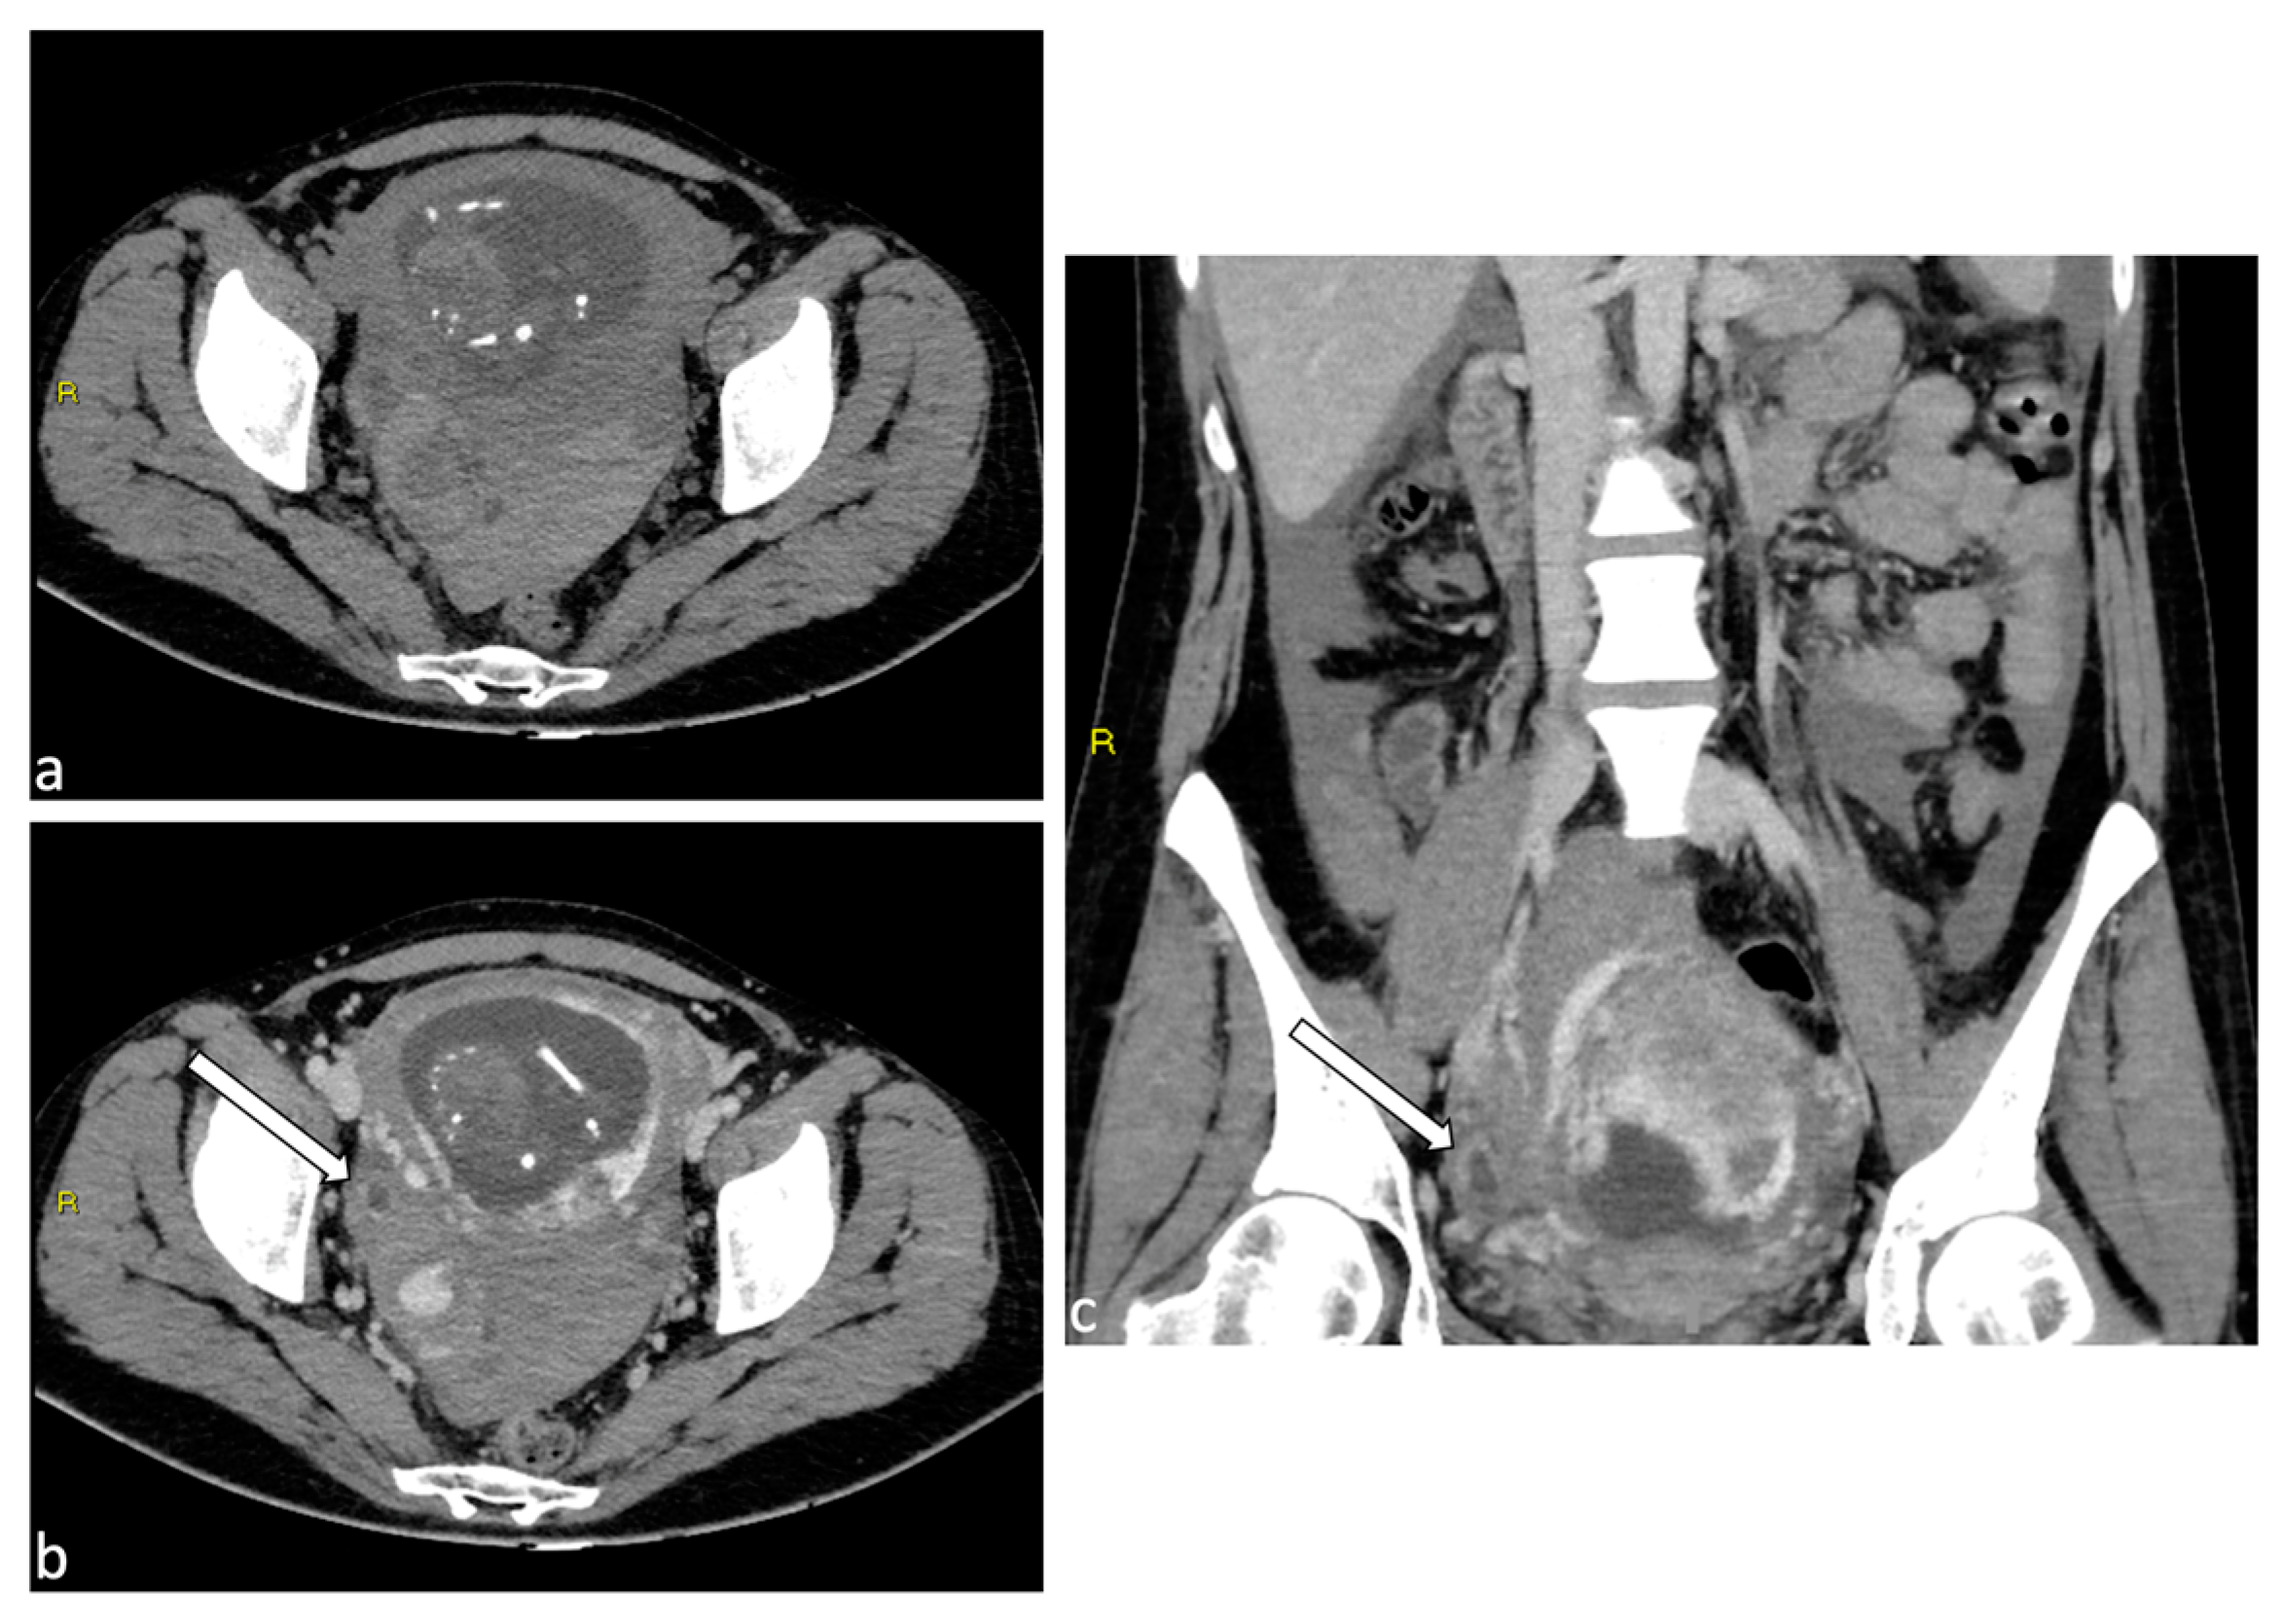

Figure 9.

Placenta percreta. A 38-year-old woman at 27 weeks of gestation with placenta previa percreta. Sagittal (a) and axial (b) T2W SSFSE images show a heterogeneous placental signal with some low signal intensity bands representing venous lakes (arrows). There is also a focal uterine bulge with thinning of the overlying myometrium. The patient underwent a caesarean section and extraction of the fetus but no secondment due to placenta percreta. In the post-partum MRI (c), signs of placental percreta were still present with an image of bladder infiltration (arrow), later confirmed at cystoscopy. It was decided to perform endovascular devascularization of the placenta percreta left in situ before proceeding to hysterectomy. Preliminary arteriography of the abdominal aorta documented hypertrophy of both uterine arteries, clearly greater on the right, which exuberantly vascularized the hypertrophied placenta, supplying multiple intraplacental high-flow vascular lakes (d). After superselective catheterization with a coaxial microcatheter of both uterine arteries and some of their distal branches, bilateral embolization was performed by infusion of a suspension of embolizing particles. The procedure was completed with release of 3 platinum microspirals (3 mm diameter) at the level of the distal right uterine artery (e), proximal to the origin of the main collaterals and 2 microspirals (3 mm) at the origin of the left uterine artery. At the end of the operation, satisfactory uterine and placental devascularization was shown (f).